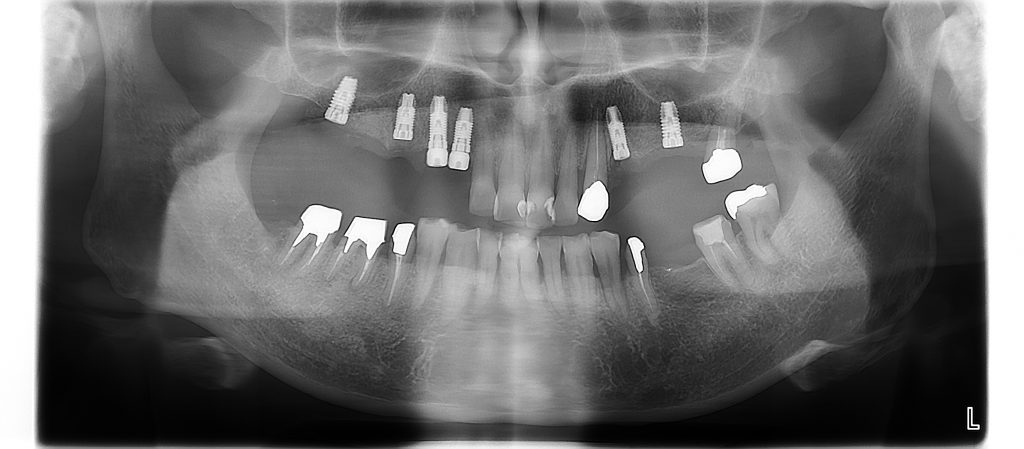

本日は上顎に6本のインプラントを埋入しました。

CT画像とサージカルガイドを用いてインプラントの手術を行いました。

インプラント埋入後

今回の処置はただ、インプラントを埋入するだけでなく、骨の少ないところには人工の骨を使った再生治療なども行いました。その為、3ヶ月程待ってから被せ物の準備をしていきます。